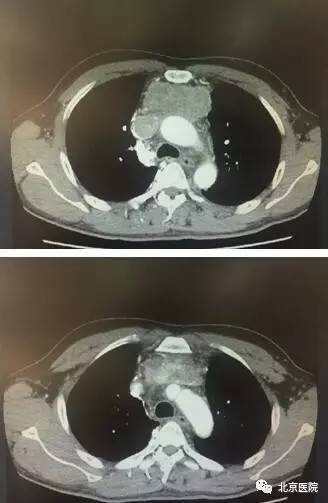

患者术前、术后对比

该患者系43岁男性,2周前出现颜面部肿胀,晨起明显,近1周来颜面部肿胀逐渐加重,颈部浅静脉怒张,前胸壁皮下静脉迂曲扩张。胸部CT提示前纵隔恶性肿瘤,外侵明显,与周围组织界限难以分清;左无名静脉及上腔静脉内瘤栓形成,上腔静脉几乎完全堵塞。面对如此复杂的病情当地医院难以完成如此复杂的手术,患者为进一步治疗于2017年3月8日来到北京医院胸外科。

CT术前、术后对比

面对如此复杂、困难的手术,胸外科佟宏峰主任率领的医护团队勇于挑战、知难而上,经过详细的术前讨论和准备,制定了周密的手术计划和围术期管理方案。在手术麻醉科医护人员的大力配合与协助下,北京医院胸外科团队于2017年3月15日在全麻下为该患者实施了前纵隔肿瘤切除、双肺上叶部分切除、心包部分切除、上腔静脉切除、左侧无名静脉切除、部分右侧无名静脉切除、左侧无名静脉-右心房搭桥、右侧无名静脉-上腔静脉搭桥术。该手术共历时5个小时,完整切除前纵隔恶性肿瘤,并顺利完成血管重建。术后经过严密的监测、精心的治疗及护理,该患者恢复顺利,上腔静脉梗阻的症状明显缓解,复查胸部CT显示重建的血管内血流通畅,效果良好,术后第7天顺利出院。